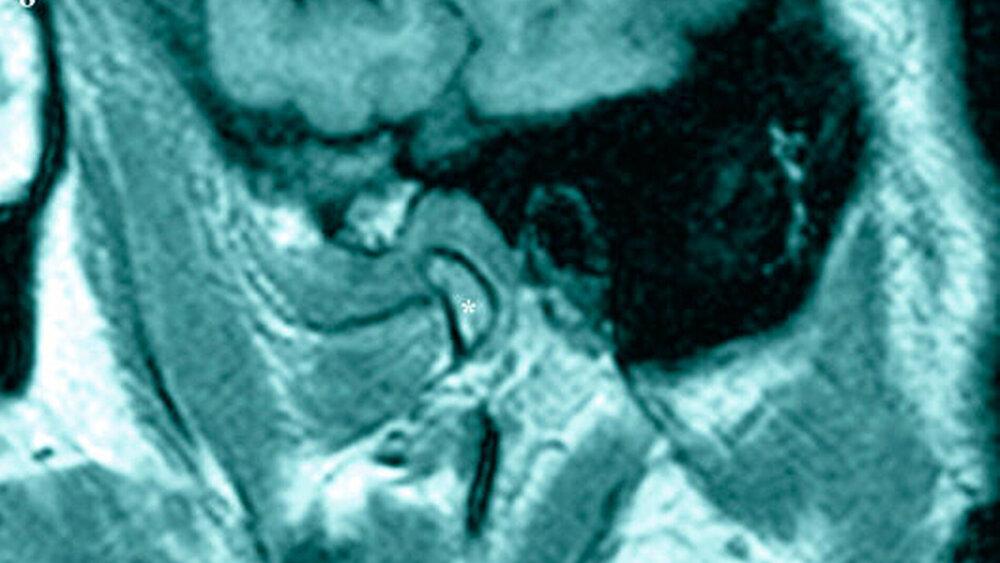

Differenzialdiagnostisch soll ein akutes entzündliches Geschehen mit topografischer Nähe zum Kiefergelenk ausgeschlossen werden. Des Weiteren kann eine Fraktur im Bereich des Collums, des Jochbeins und/oder des Jochbogens zu einer Kieferklemme führen. Weiterhin können durch Strahlentherapie bedingte Kontrakturen ursächlich sein. In seltenen Fällen kann es nach operativer Weisheitszahnentfernung und ausgedehnter postoperativer Schwellung zur Bildung einer Narbenkontraktur kommen. Differenzialdiagnostisch sollte auch an Kiefergelenkserkrankungen wie Diskusverlagerungen (Abbildung 8), Ankylosen und Tumore gedacht werden.